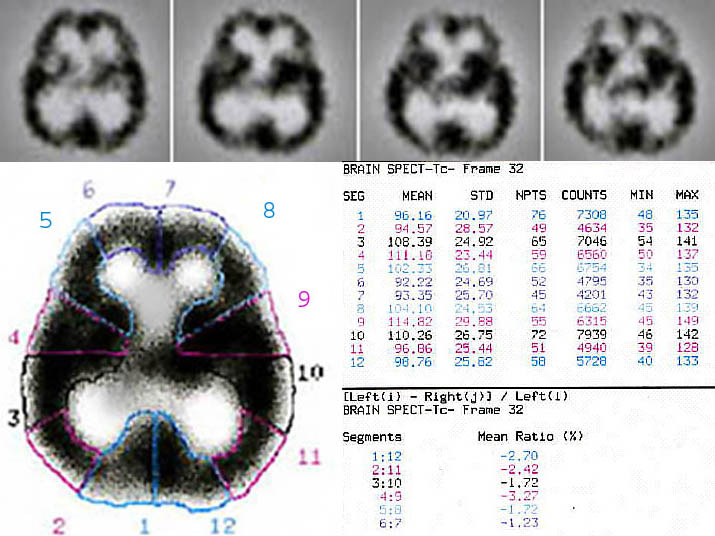

Supporting software includes dynamic filters, multiple angle reconstructions, surface variable attenuation corrections, three dimensional/conventional /cross sectional displays. The computer then reconstructs 3-D images of the brain (Figure 1). With these brain maps, physicians are able to identify certain patterns of brain activity in different psychiatric and neurological problems. Basically, in a typical brain SPECT we are looking for an asymmetry and different activity levels and comparing it to what we know as a normal brain (Figure 2). A normal SPECT image reveals homogeneous and uniform tracer accumulation throughout the cerebral cortex, with the cerebellum being the area with the most intense activity [24, 26, 28].

Figure 1

Quantification of regional involvement in schizophrenia; a sample of 99mTc-ECD-Brain SPECT data analysis in a schizophrenic patient. Data was processed by a DSX computer vision (revision-7.0) and picture reconstruction was performed by using Butterworth filter with automatic attenuation correction. Single-photon-emission-computed-tomography, as its name might suggest, relies heavily on computers to acquire, process and display the SPECT image. As image processing software and hardware become smaller, faster and just "better", SPECT will adapt and incorporate those advances it can use. It is hoped that improvements in parallel processing and computer architectures will make Bayesian reconstruction faster and take less computer memory, and thus make it more attractive for potential use in the clinic.